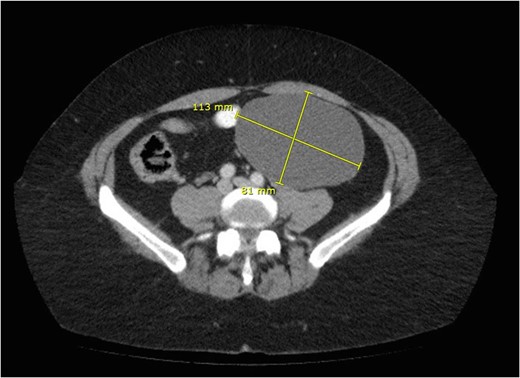

A mesenteric cyst is rare intra-abdominal pathology, with little literature to guide us on how to diagnose and manage it. We report the incident of a 57-year-old female who had an incidental finding of a sigmoid mesenteric cyst whilst undergoing an operation under the care of the Gynaecologists. A computed tomography scan and a flexible sigmoidoscopy followed to help diagnose the lesion as a cyst. A month later the 10 × 15 cm2 cyst was excised laparoscopically with no complications.

Mesenteric cysts are rare intra-abdominal lesions [1–4]. They occur in both adults and children with an incidence of 1/10 500–25 000 of adult surgical patients [5]. They are mostly found incidentally but patients with these cysts can sometimes present with non-specific complaints of abdominal pain and distension, or an abdominal mass [1]. They commonly originate in the small bowel mesentery, mesocolon (24%), retroperitoneum (14.5%) and very rarely from the sigmoid mesentery [6]. To diagnose these cysts, patients often require radiological investigations such as ultrasonography (USS), computed tomography (CT) and magnetic resonance imaging (MRI) [7]. Depending on their symptoms and location, these cysts can either be treated conservatively, or by open or laparoscopic surgical excision, and histological examination is often required to identify the origin of the cyst.